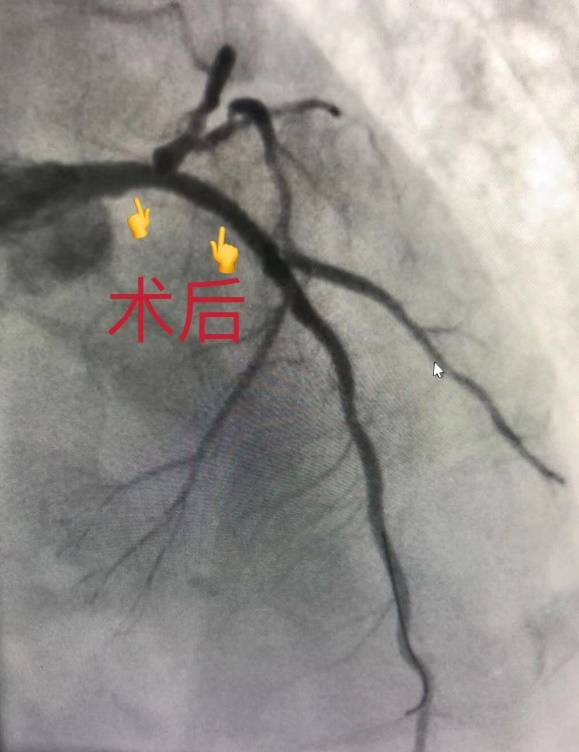

术者翁建新主任医师和黄谦文医生在术中发现,吴先生的心脏血管中:左主干80%被堵塞,左前降支近段90%被堵塞,回旋支及右冠状动脉均80%被堵塞。手术团队依据手术方案,在关键的左主干及左前降支近段病变处植入一枚支架,解除了血管狭窄,使心肌恢复充分的供血。手术团队技术纯熟、准备充分,手术过程十分顺利。

手术前,吴先生被堵塞的心血管;植入支架后,堵塞的心血管开通。